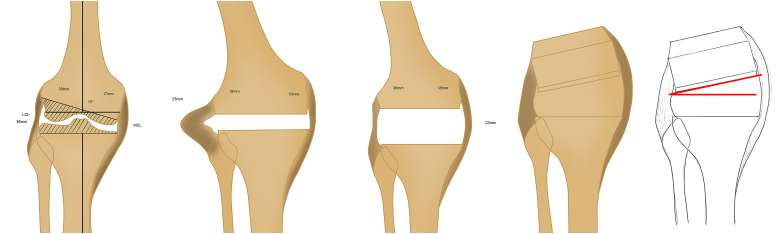

5.1. Primary TKA

Tibial resection affects both flexion and extension gap equally. Although single-stage, intra-articular resection does not require simultaneous osteotomy, it will require soft tissue release. Intra-articular correction of an extra-articular varus deformity requires removal of more lateral than medial femoral condyle and conversely a valgus deformity will require greater medial resection.9 In both situations, this asymmetric resection will result in imbalance of the soft tissues (Fig. 3a–d). More specifically, pre-operative femoral or tibial varus deformity will, post-resection, result in laxity of the lateral soft tissue structures and therefore will require medial soft tissue release, which may in turn alter the joint line, potentially causing patella-femoral problems.

Fig. 3.

Hypothetical case - Images Courtesy Kevin Tetsworth, Brisbane, Australia3a – 15 degrees extra articular femoral shaft deformity – Femoral asymmetric cut and tibia neutral cut3b – lateral ligament laxity due to asymmetric cut3c – MCL release – extension gap balanced3d – Flexion gap not balanced with MCL laxity.

Femoral or tibial valgus deformity post-resection will result in laxity of the medial structures requiring release of the lateral structures. Lateral collateral laxity is better tolerated than medial collateral laxity and therefore the surgeon can perhaps correct slightly more varus than valgus. Similarly, the superficial medial collateral tibial attachment is further removed from the joint line compared with its femoral attachment and therefore, the surgeon can perhaps correct slightly more deformity on the tibia than on the femur.

Femoral asymmetric cuts affect extension and flexion unequally, creating a more challenging problem; there may be difficulty in achieving satisfactory patella-femoral alignment and tracking and there can be difficulty in achieving varus-valgus stability in mid-flexion. The joint line may be raised, increasing the patella-femoral joint load; this may not show up in early outcome measures, but may then present as later symptoms (Fig. 3a–d).

It is possible that despite some increase in patella-femoral joint loading, correction of deformity that involves a few millimetres of additional excision medially or laterally on the distal femoral cut, appropriately accommodated in flexion by slight rotation of the femoral component, may give acceptable functional outcomes.

It is suggested therefore that the asymmetric cuts method may be useful for minor malalignments but in view of the potential long-term effects, the authors recommend avoidance of this method in severe deformities .